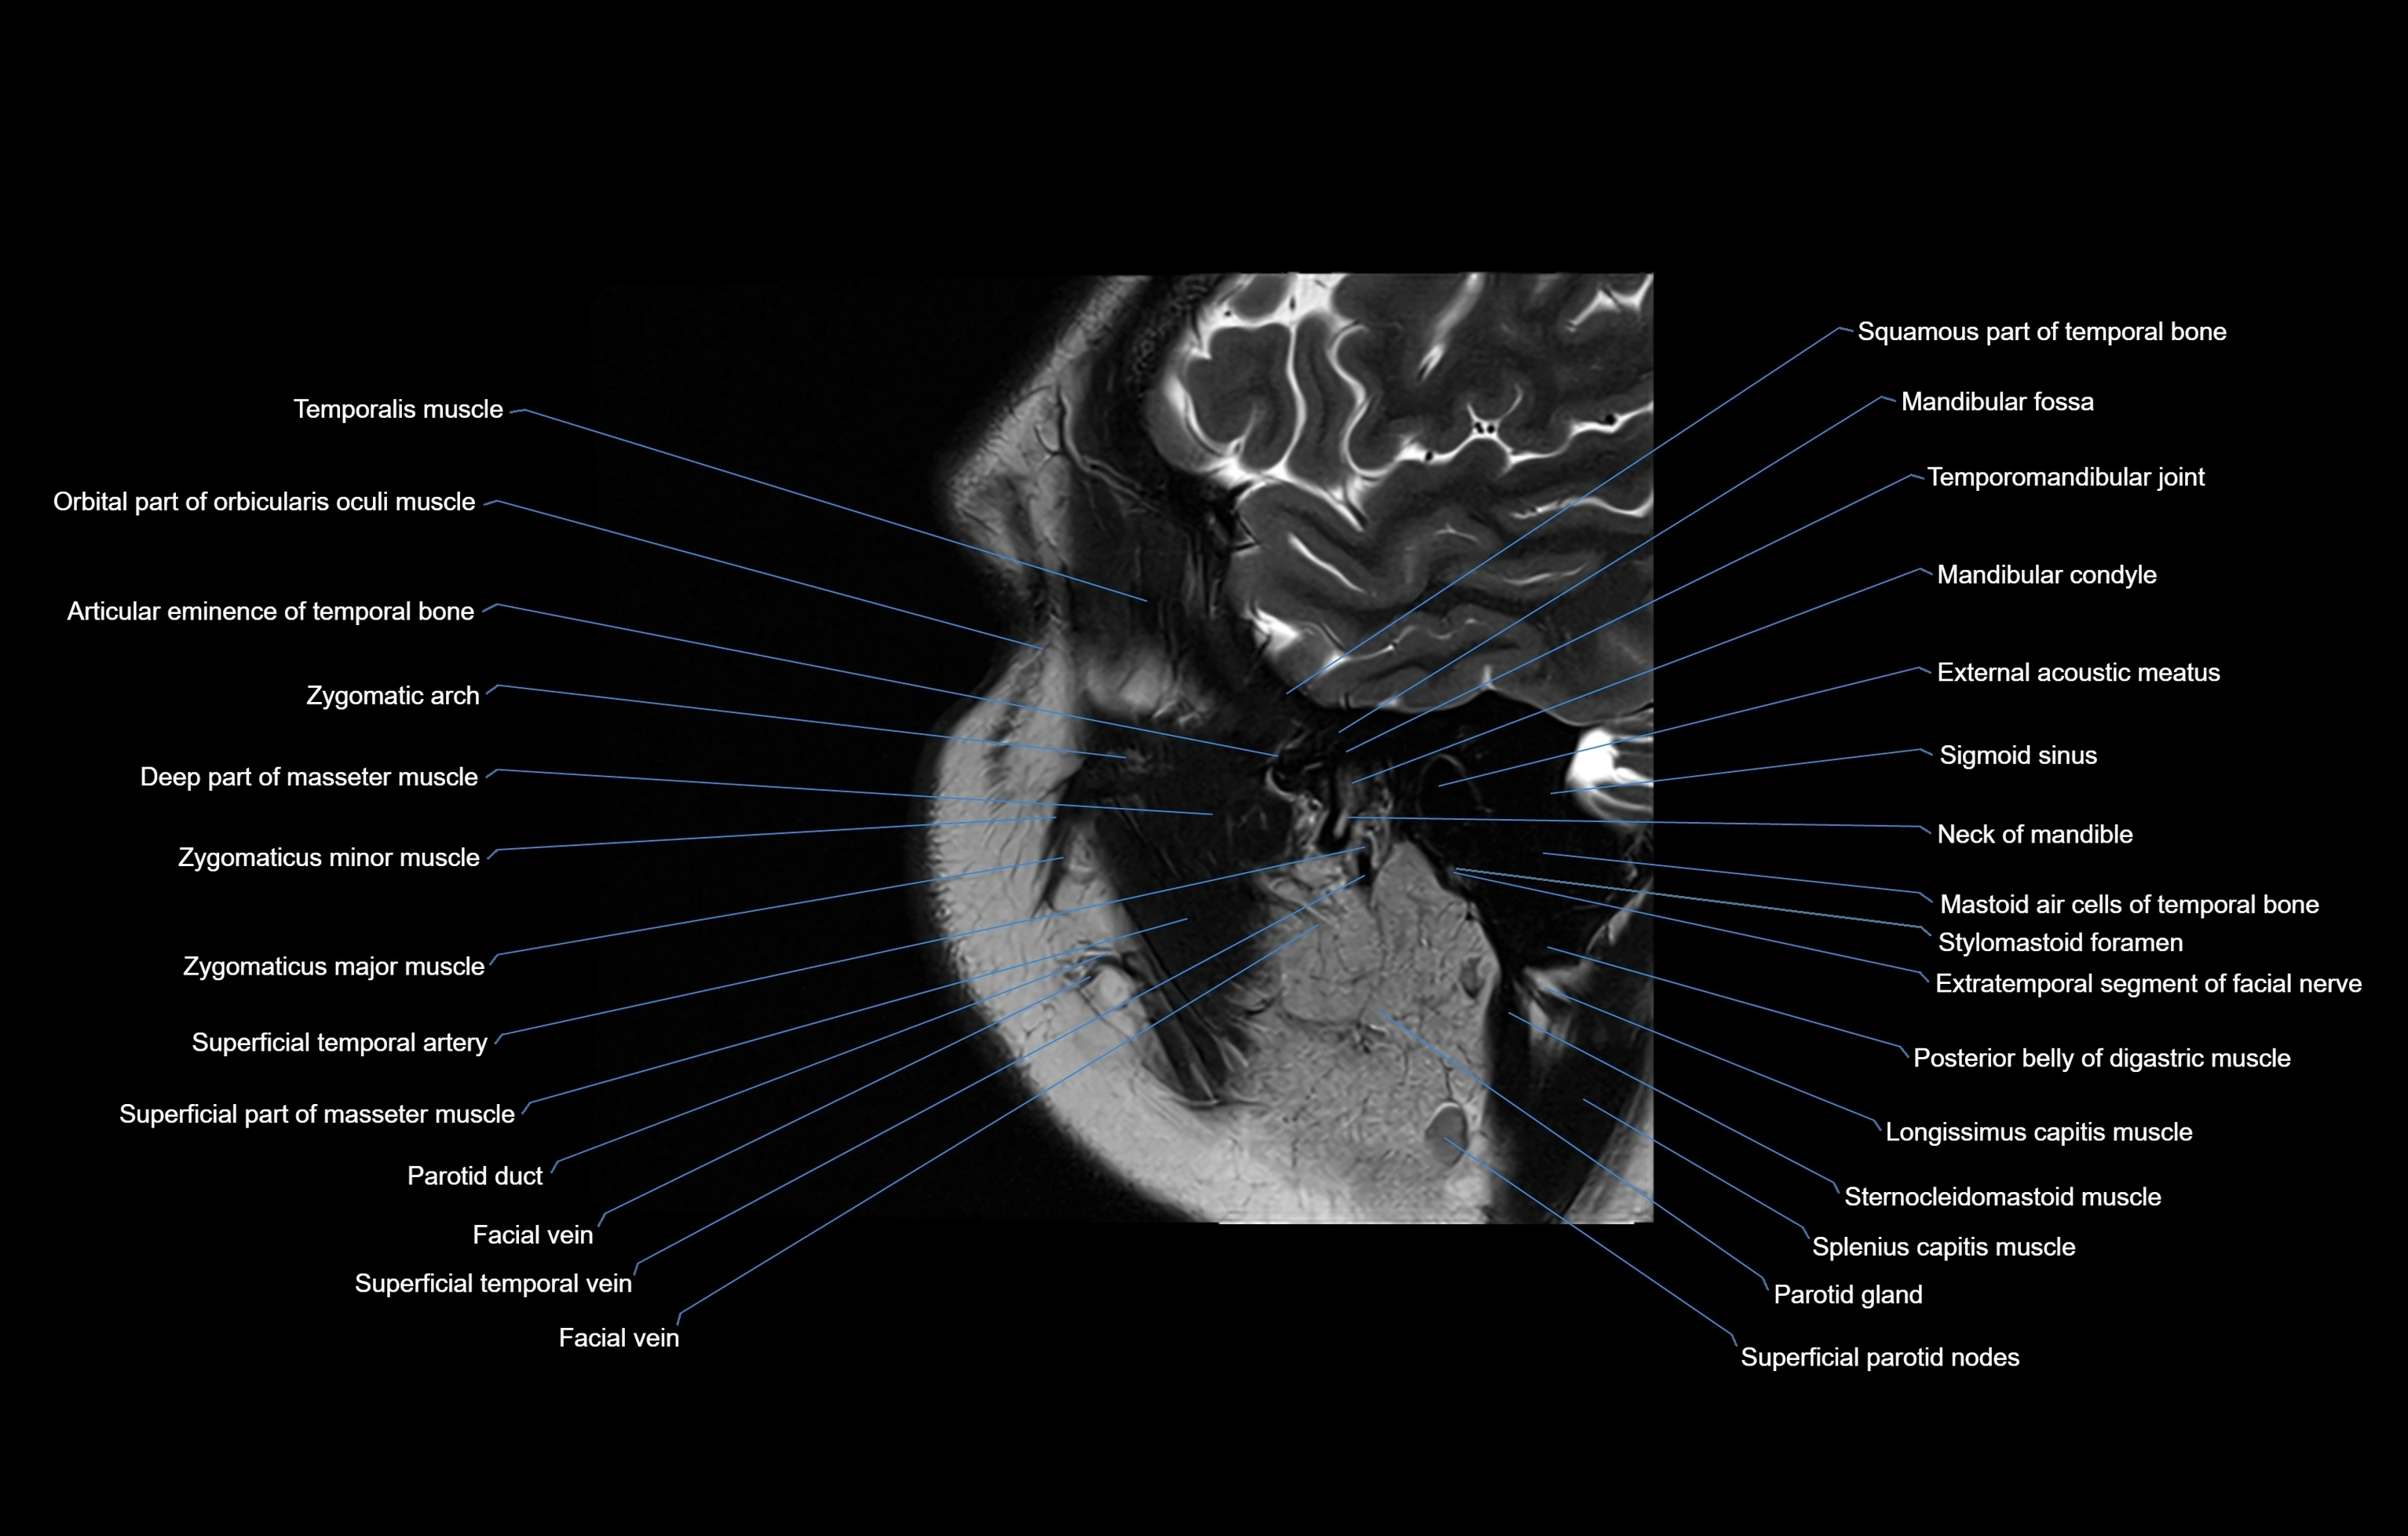

MRI images